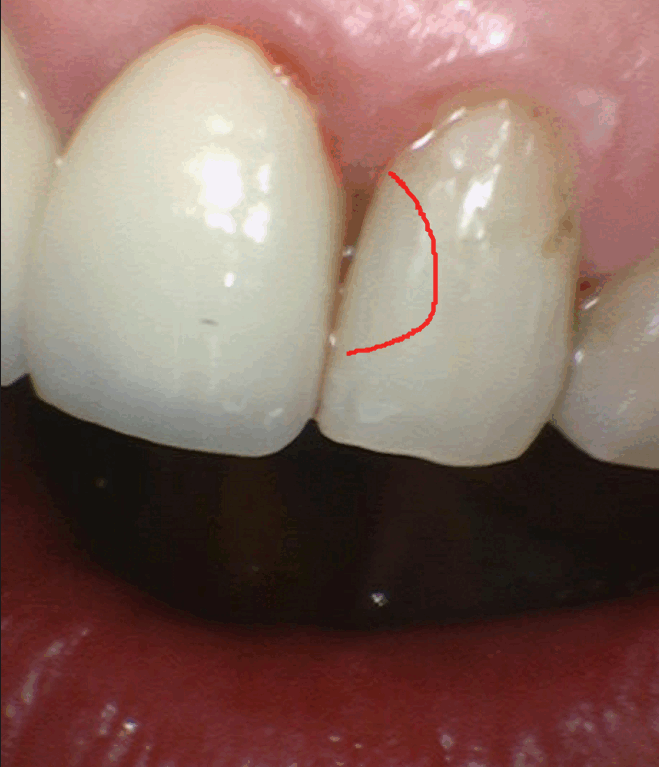

231127

치아 뒤쪽에 까맣게 비춰보이는 부위가 충치입니다.

조심스럽게 제거를 해보겠습니다~